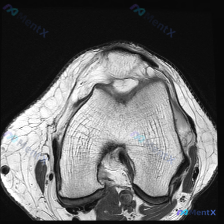

看到这个读片病例,感觉很有代表性,整理了资料和分析思路分享给大家。 病例影像基本信息 本次为膝关节MRI T2序列轴位影像,扫描层面位于股骨髁水平,可见髌骨及股骨滑车关节面,影像所见整理如下: 1. 骨骼软骨:股骨髁骨皮质连续,未见骨折;髌骨形态骨髓信号基本正常;髌股关节软骨信号均匀,轮廓基本连续,...

看到这张膝关节MRI T2轴位影像,整理了完整的分析思路分享给大家。 一、影像基本信息 本次分析仅为单张膝关节髌股关节层面的T2轴位图像,核心所见如下: 1. 髌骨后方软骨面可见信号增高,轮廓尚完整,软骨下骨板下方信号略不均匀 2. 股骨滑车沟软骨表面信号稍不均匀,髌股关节间隙及侧隐窝可见较明显T2...